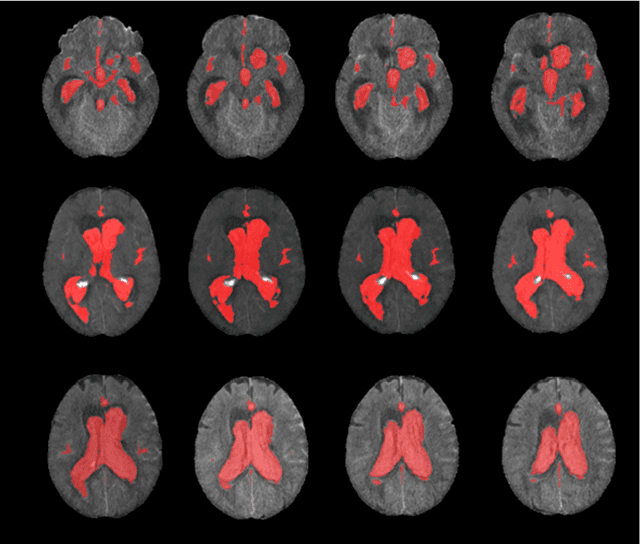

Abstract:Background: Accurate volumetric assessment of spontaneous subarachnoid hemorrhage (SAH) is a labor-intensive task performed with current manual and semiautomatic methods that might be relevant for its clinical and prognostic implications. In the present research, we sought to develop and validate an artificial intelligence-driven, fully automated blood segmentation tool for SAH patients via noncontrast computed tomography (NCCT) scans employing a transformer-based Swin UNETR architecture. Methods: We retrospectively analyzed NCCT scans from patients with confirmed aneurysmal subarachnoid hemorrhage (aSAH) utilizing the Swin UNETR for segmentation. The performance of the proposed method was evaluated against manually segmented ground truth data using metrics such as Dice score, intersection over union (IoU), the volumetric similarity index (VSI), the symmetric average surface distance (SASD), and sensitivity and specificity. A validation cohort from an external institution was included to test the generalizability of the model. Results: The model demonstrated high accuracy with robust performance metrics across the internal and external validation cohorts. Notably, it achieved high Dice coefficient (0.873), IoU (0.810), VSI (0.840), sensitivity (0.821) and specificity (0.996) values and a low SASD (1.866), suggesting proficiency in segmenting blood in SAH patients. The model's efficiency was reflected in its processing speed, indicating potential for real-time applications. Conclusions: Our Swin UNETR-based model offers significant advances in the automated segmentation of blood after aSAH on NCCT images. Despite the computational intensity, the model operates effectively on standard hardware with a user-friendly interface, facilitating broader clinical adoption. Further validation across diverse datasets is warranted to confirm its clinical reliability.